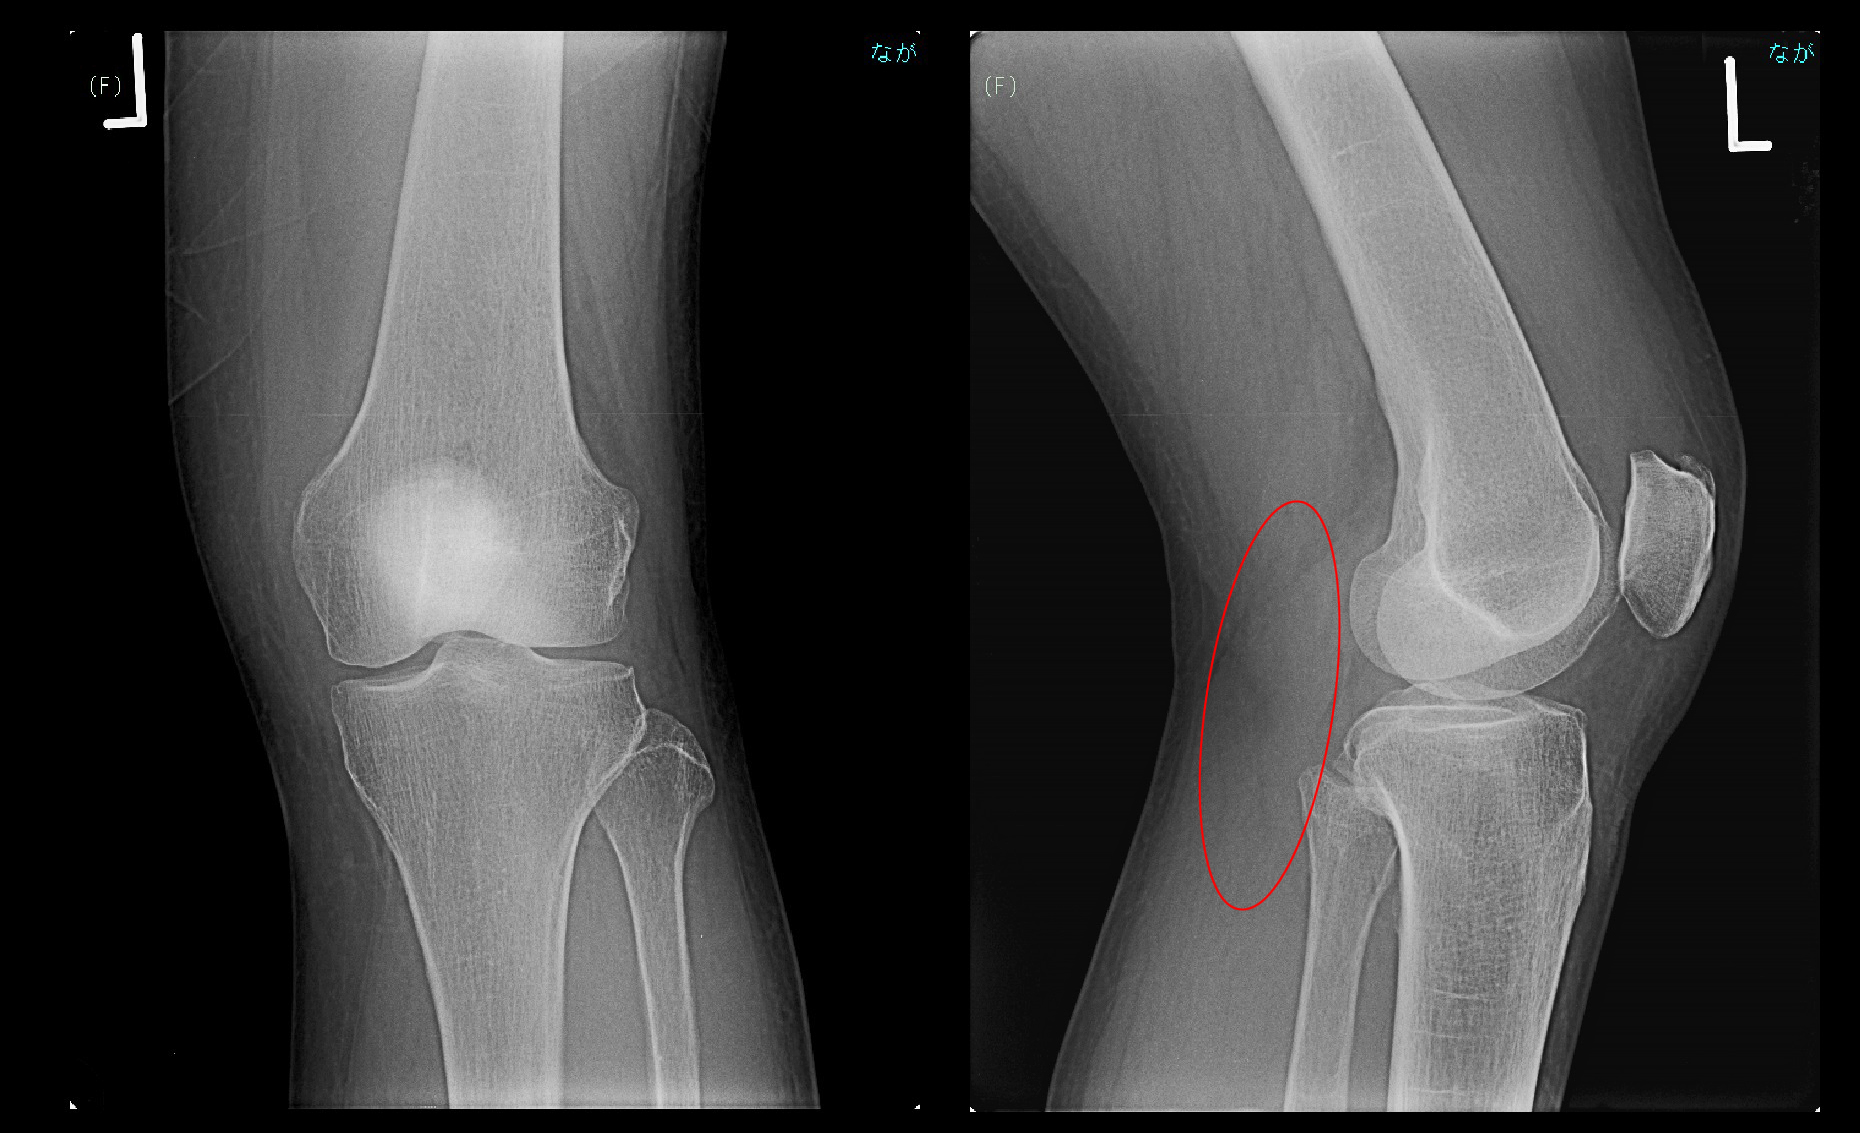

63才女 MR1.jpg

GR冠状断(前後像)ですが、当時は赤矢印の左膝内側半月板の変性(=損傷)にのみ目が行き、それに起因する左膝痛と診断していました。令和6年10月にこの画像を見直しては黄色矢印で左膝内側半月板は後根部が白くなっており、後根損傷が起きていたことを把握しました。

63才女 MR2.jpg

さらに令和6年のMRI画像の見直しでは、内側半月板の亜脱臼も確認され、後根損傷が明瞭に診断されました。Kさんの左膝痛は治りにくいタイプの加齢性の状態(変形性膝関節症の初期)であったと理解して良いと思います。4月26日からヒアルロン酸の関節注射を開始していますが、5月28日にはKさんは「治りますか?」と質問しており、後根損傷や亜脱臼について認識していなかった当時の私は「治ります。月単位で経過をみてください。」と答えています。6月24日にも10月1日にもKさんからは「ダンスができない」と訴えられています。7月1日から2度目の連続5回のヒアルロン酸の左膝関節注射を行っています。10月30日に階段の昇降が慎重に交互にできるようになったと報告されていて、11月15日に私はダンスに少しづつ挑戦してみてくださいと言っています。そして12月10日以後受診がなくなりました。初診後8か月経過していました。